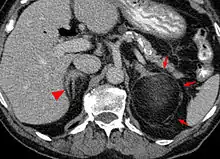

Myeloplipoma shown on a CT scan image

Most myelolipomas are unexpected findings on CT scans and MRI scans of the abdomen. They may sometimes be seen on a plain X-ray films.[4]